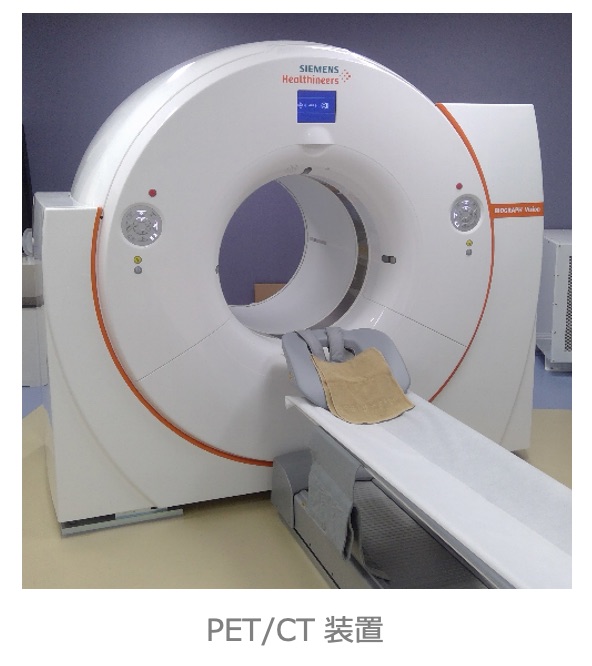

核医学検査(RI 検査)

放射性同位元素(Radio Isotope:RI )を用いた検査のことで、目的とする臓器や腫瘍に集まる薬にRIで目印を付けて投与し、放出される放射線(ガンマ線)を専用のカメラで計測します。 核医学検査はSPECT(スペクト)とPET(ペット)に分けられ、さらに心臓、脳、肺、骨、腫瘍など検査目的によって多くの検査に分けられます。

当院の核医学検査(PET検査、SPECT検査)は核医学専門技師の認定を受けた診療放射線技師を中心とし、放射性医薬品の管理や機器精度管理のもと撮影を担当しています。

●PET/CT検査

⼀⽅、X線CT は⾝体の外からX線をあて、X線の影、すなわち臓器の「かたち」を画像化する検査です。PET/CT装置はPETとX線CTの複合機で、両者を組み合わせた情報が得られます。